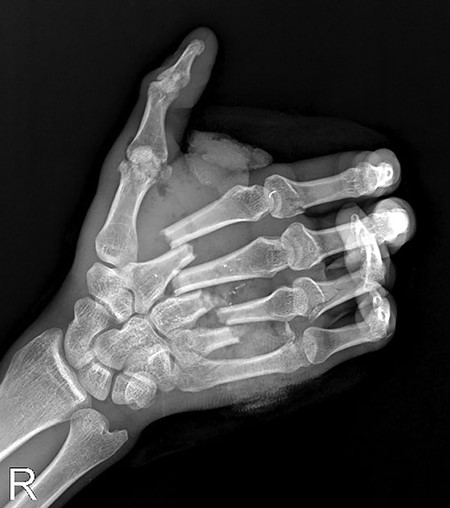

A 27-year-old male was admitted to the emergency room after blunt trauma on the dorsum of the right hand. In his physical examination, circulation and sensory findings were normal, but the motor functions were limited. On the X-ray radiograph, metacarpal base fractures were detected in the index, middle and ring fingers (Figs 1 and 2). After the surgical area was sterilized, the dissection was initiated under tourniquet and general anesthesia. Tendons were found to be intact due to blunt trauma, and the metacarpal base fractures in fingers were exposed (Fig. 3). These bones were stabilized with Kirschner wires (Fig. 4). After the debridement of dead tissues and opening the tourniquet, bleeding was controlled, and skin was stapled. The flap was planned for the 2 x 2 cm defect, which corresponds to the third metacarpal bone and exposed the tendon and bone (Fig. 5). The first dorsal metacarpal artery (FDMA) flap was initially considered; however, a dorsoradial artery flap was preferred since the dissection reached to the second metacarpal bone.